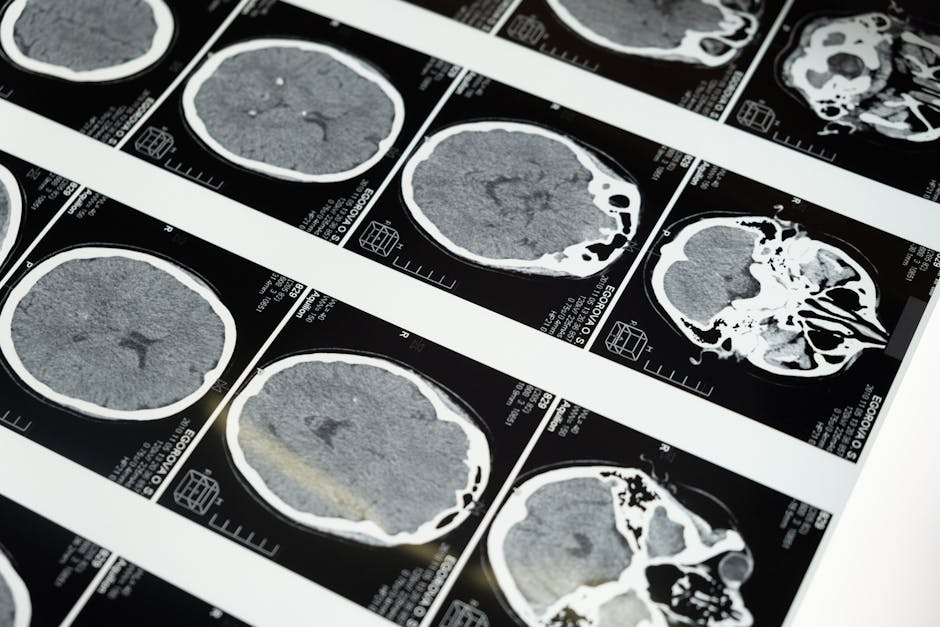

Pour cette raison, une prise en charge multidisciplinaire impliquant neurologues, ophtalmologues et dentistes est souvent recommandée. L’imagerie médicale, bien que non spécifique de l’AVF, peut aider à éliminer d’autres pathologies organiques.